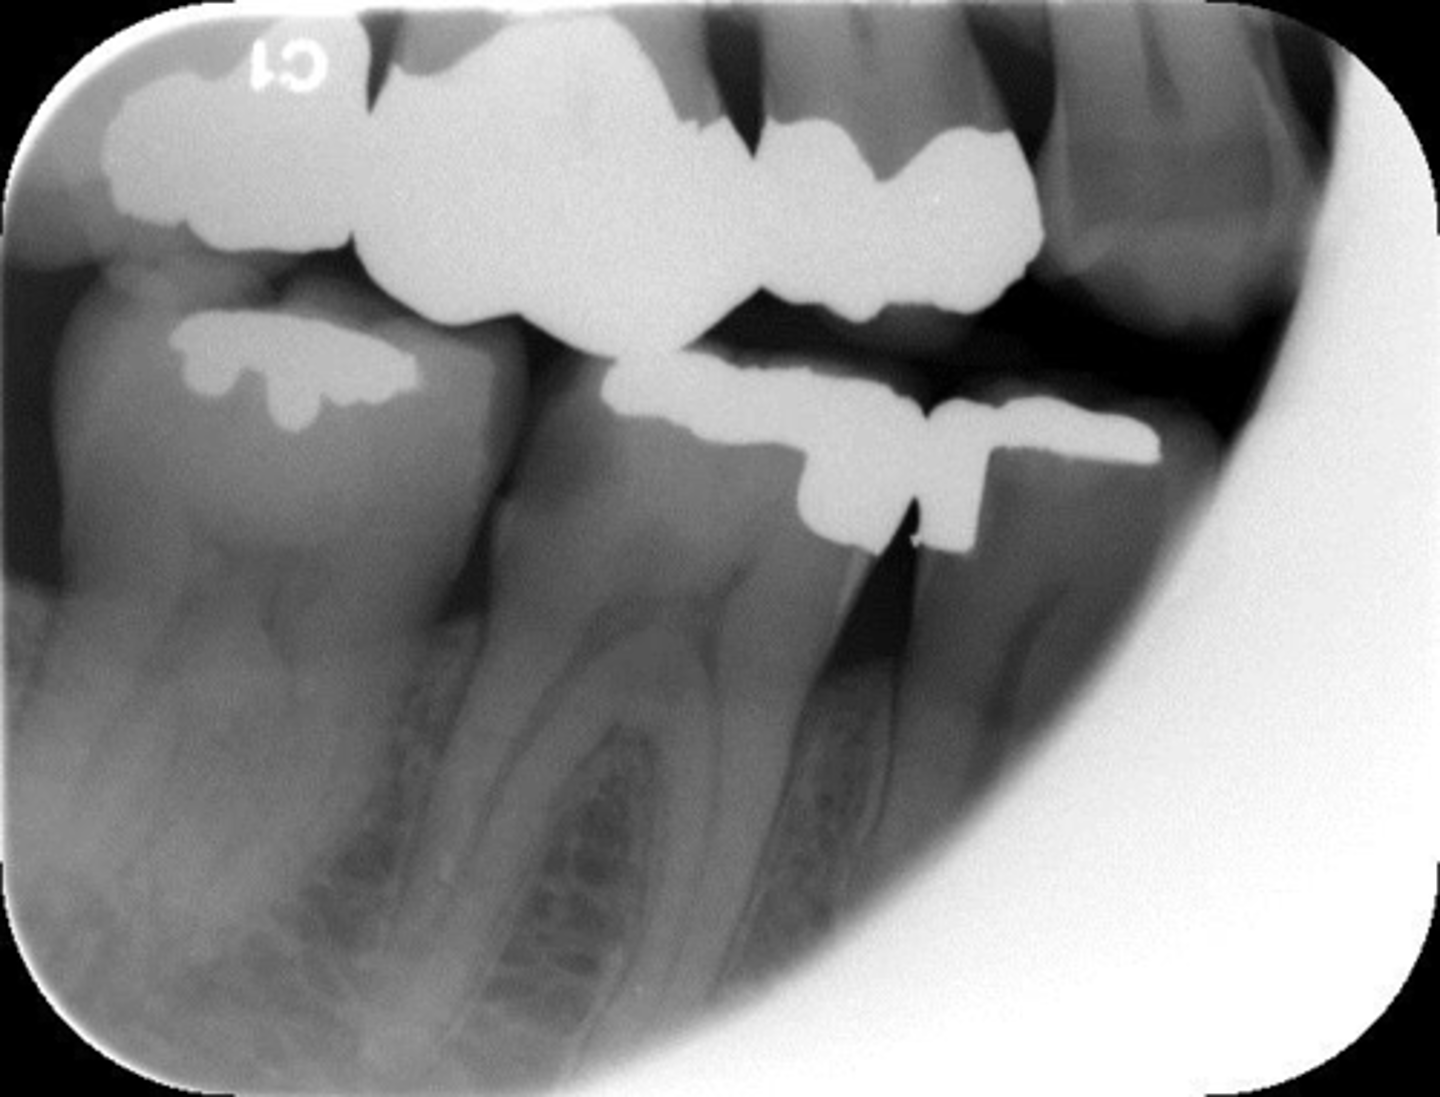

Horizontal angulation, no apices show, vertical angulation

What is this error?